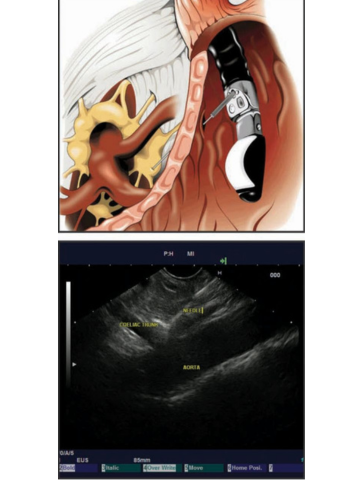

Початкова розробка EUS-FNA прогресувала, щоб забезпечити нові та нові терапевтичні показання для ЕНДО УЗД. Блокування целіакічного сплетення та нейроліз за допомогою ін’єкції стероїдів або спирту під контролем EUS у черевне сплетення, а останнім часом безпосередньо в ганглії целіакії, є безпечним та ефективним методом контролю болю при раку підшлункової залози та, меншою мірою, при хронічному панкреатиті (мал. 4).